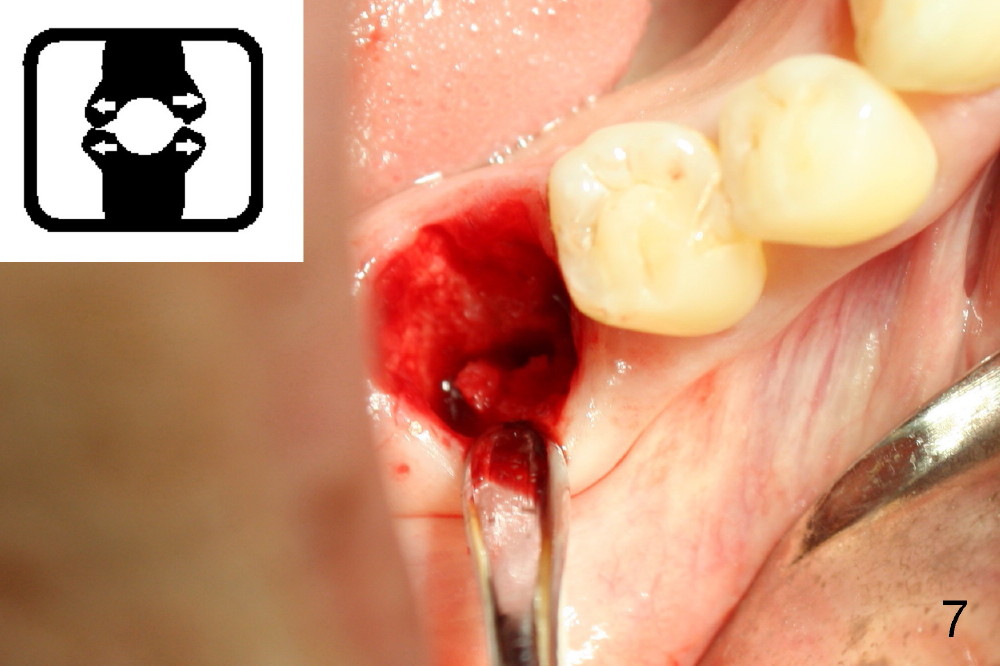

A sixty-year-old lady fractured the crown of the lower right first molar (Fig.1). The residual roots were sectioned (Fig.2 between arrowheads) and removed. The septum (Fig.3 *) is round on the top between mesial and distal sockets (1,2). Thin osteotomes (bone scalpel, bone blade; Fig.4: T) were used to section the septum mesiodistally. Fig.5 shows the sectioned septum, which makes it easy to insert round tapered osteotomes (Fig.5 inset green; Fig.6 R) without slipping either into the mesial or distal socket.

Septal bone is apparently pushed into the mesial and distal sockets (Fig.7 inset arrows) when a small round osteotomes is removed. The deeper portion of osteotomy is created by drills (Fig.8,9). The septal bone is further pushed mesiodistally as the osteotomy enlarges with combination of drills and osteotomes (Fig.10). A 6x17 mm tapered implant is placed with insertion torque >60 Ncm (Fig.11: I).